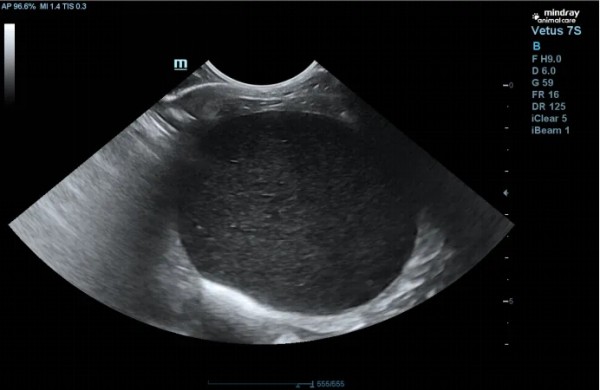

一、引言 猫痤疮是猫下颌、嘴唇部位一种常见的毛囊角质化疾病,本质是毛囊角化异常,导致粉刺(黑头)形成。轻度病例可能仅影响美观,但可继发细菌感染,发展为毛囊炎、疖病,甚至蜂窝织炎。治疗需根据严重程度分级进行,核心是局部清洁、角质溶解和控制感染。预后良好,但易复发,常需长期护理。本文报告一例9岁雄性已去势英国短毛猫因严重下颌皮肤病就诊的病例。患猫表现为严重的下颌皮肤的蜂窝织炎、食欲减退及精神沉郁。通过临床检查、细胞学及炎症指标检测,确诊为猫痤疮伴发严重的蜂窝织炎。治疗采用局部清创消毒、药用香波清洁、外用抗菌药膏,并联合系统性抗生素(阿莫西林克拉维酸钾)及情绪安抚药物进行综合管理。经过两周治疗,患猫临床症状完全缓解。本病例强调了猫痤疮继发感染时的综合诊疗思路,强调了猫痤疮的治疗总原则:局部清洁、溶解角质、控制继发感染。 二、基本信息 动物:9岁,雄性已去势,英国短毛猫,体重4.8公斤。 生活史:免疫驱虫完全,定期(每三月一次)洗澡。 主诉:近期出现频繁抓挠下巴及颈部行为,导致该部位皮肤破损出血,伴随食欲欠佳、活动量减少。 既往史:无相关病史记录。 三、检查项目及结果 就诊时照片 挤压病变处分泌物涂片,进行染色镜检。可见大量退行性嗜中性粒细胞和巨噬细胞 皮肤刮片检查:未见寄生虫 血检:WBC:28.7; Neu:13.06;SAA:67.83; 结果:B超扫查发现,膀胱充盈,膀胱壁欠光滑,腔内充满产回声内容物,提示膀胱内有泥沙样结晶。 四、诊断结果 病史与临床检查:根据特征性的发病部位(下颌)和临床症状(粉刺、丘疹等),通常可做出初步诊断为猫痤疮。病因待进一步确认。 五、治疗方案及预后 剪短患处毛发,注意不是剃毛以防进一步的毛囊应力损伤,给患处消毒,每周1-2次用泡泡爽宠物清洗剂清洁,每日涂抹抑菌膏,口服阿莫西林克拉维酸钾干混悬剂(克维舒),每次1ml,一日两次;配戴脖圈,防止抓挠,每日两次宠物情绪调节营养补充剂(舒欣宝)每次1条缓解瘙痒情绪,治疗2周病变处症状显著改善。继续使用一周抗生素。 清洁后的照片 治疗第一周的照片 治疗第二周,痊愈照片 六、讨论及小结 猫痤疮为猫常见的一种皮肤病,为下颌组织及腺体的囊泡性角化及腺体增生,此病例为中重度的猫痤疮,继发细菌感染,引起毛囊炎、疖病。表现为疼痛性肿胀、囊肿、瘘管,按压有脓血排出。除了局部清洁用药外,同时使用抗生素治疗控制继发感染,并使用情绪舒缓产品辅助治疗,本次治疗我们选用了更适宜猫咪的口服抗生素与情绪舒缓产品。首要考量是避免因强制喂药牵扯下颌,引发额外疼痛;同时,我们也希望借助更易喂服的口服片剂,来降低宝贝的紧张感,从治疗本身提升它的就医体验。 阿莫西林和克拉维酸钾(克维舒)适应证:犬用于治疗犬由产β-内酰胺酶的金黄色葡萄球菌,不产β-内酰胺酶的金黄色葡萄球菌,葡萄球菌属,链球菌属和大肠杆菌引起的皮肤和软组织感染,如创伤、脓肿、蜂窝织炎、浅表性/幼年性和深层脓皮病;由需氧和厌氧敏感菌引起的牙周感染。猫:用于治疗猫由产β-内酰胺酶的金黄色葡萄球菌,不产β-内酰胺酶的金黄色葡萄球菌,葡萄球菌属,链球菌属,大肠杆菌,多杀性巴氏杆菌和巴氏杆菌属引起的皮肤和软组织感染,如创伤、脓肿、蜂窝织炎。 进一步探讨关于猫痤疮难治性或慢性病例的考虑 对于常规治疗无效的病例,可考虑以下方案: 维生素A:口服维生素A或外用维A酸软膏(Retin-A)。注意:维A酸对猫刺激性大,需非常谨慎使用,且价格昂贵。 全身性糖皮质激素:如果瘙痒和炎症非常严重,可短期口服泼尼松龙片(1-2 mg/kg,每日一次,症状控制后迅速减量),以打破瘙痒-感染的恶性循环。但需谨慎使用。 排查潜在病因:如果痤疮反复发作或治疗效果不佳,应深入排查是否存在食物过敏、过敏性皮炎等潜在问题。 预后:通常预后良好。但猫痤疮是一种慢性、易复发的疾病,很多病例需要终生间歇性的对症治疗和护理。 给主人的建议: 1. 坚持日常护理:症状缓解后,仍需定期使用药用香波清洗下颌(如每周1次),作为预防。 2. 使用陶瓷或不锈钢食盆:避免使用塑料食盆,因其表面易刮擦藏匿细菌。 3. 保持清洁:饭后擦拭猫的下颌,保持该区域干燥清洁。 4. 避免刺激:切勿用手挤压粉刺,这会加重炎症和感染。 5. 遵从医嘱:如果医生开了抗生素,务必完成整个疗程,不可自行停药。 七、参考文献 《猫病学》 第5版 《小动物皮肤病学》 第7版